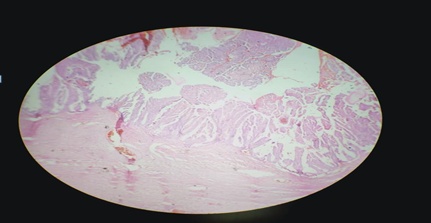

Of the 60 women who underwent a surgical procedure, histopathology of 54 specimens showed ovarian pathology. Three cases turned out to be non-ovarian pathology (paraovarian cyst) and three had normal ovarian morphology. Of the 54 cases with ovarian pathology, four had bilateral tumours so that the total number of ovarian tumours subjected to histopathological examination was 58 in all. Out of the 58 tumours, 93.10% were benign, 1.72% was borderline and 5.17% were malignant. All the malignant tumours were diagnosed as serous cystadenocarcinoma and constituted 5.17 % (fig. 1) of all the tumour cases in this study. The incidence of borderline serous tumours was 1.72% fig. 2. Surface epithelial tumors were the most prevalent among the benign tumors, accounting for 74.13% of the total. The incidence of serous cystadenomas was 44.8%, mucinous cystadenomas 22.41% (fig. 3), serous cystadeno fibromas 5.17% and mucinous cystadenoma with a component of benign Brenner’s tumor 1.72% (fig. 4). Germ cell tumours constituted 13.8% of the total, of which mature cystic teratomas accounted for 12.06% (table 4).

Fig. 3: Mucinous cystadenoma